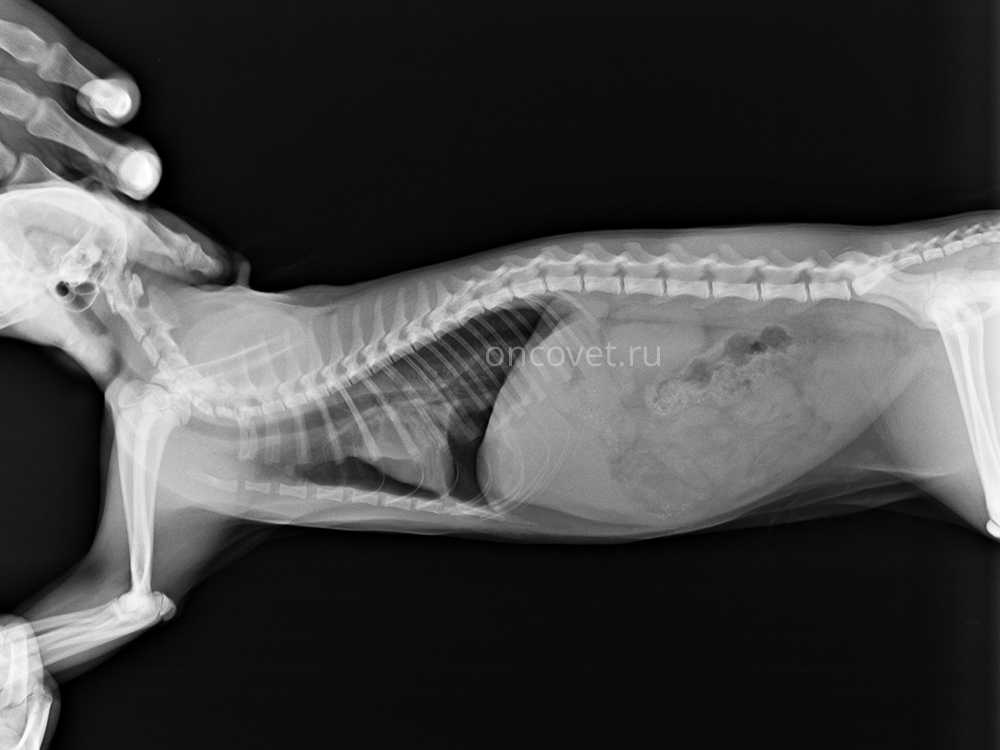

боковая проекция

Диагноз ставят на основании данных анамнеза и клинических симптомов, используя инструментальные методы диагностики, например, рентгенографию (рис.1).

Рис. 1. Пневмоторакс тяжелой степени, полученный в результате несчастного случая. Края легкого сильно отдалены от стенки грудной клетки и диафрагмы вследствие накопления большого количества воздуха в плевральной области. Увеличение плотности паренхимы легких обусловлено компрессионным ателектазом и, предположительно — контузией легких. Рентгенограмма свидетельствует о наличии клапанного пневмоторакса.